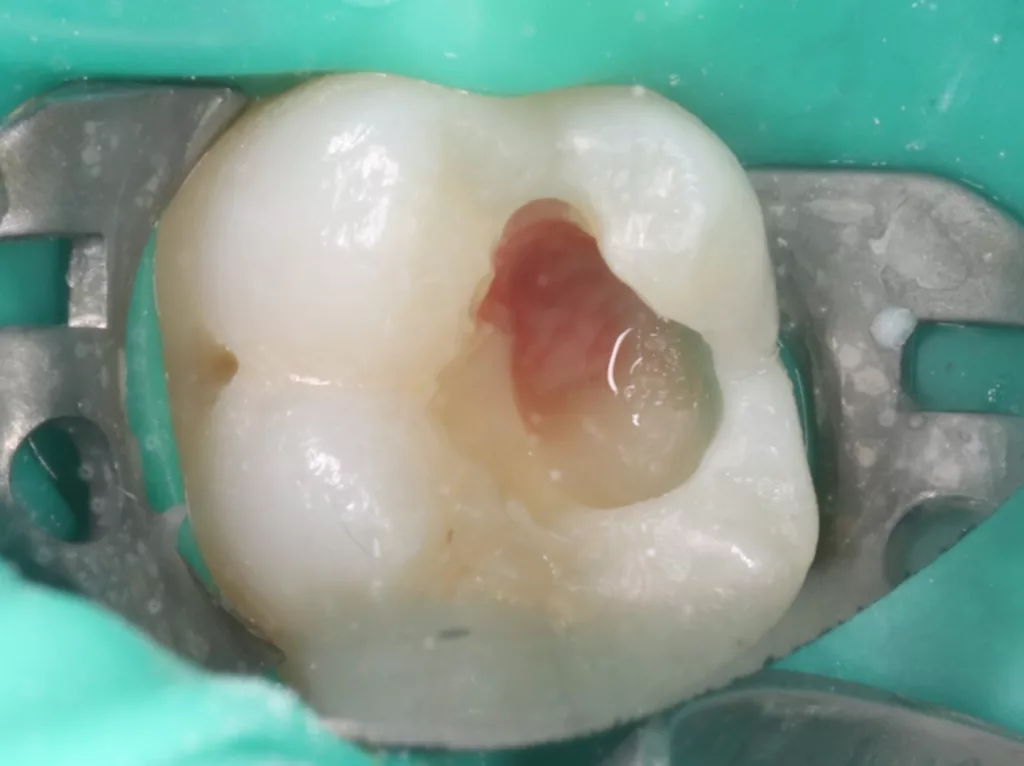

Bei routinemäßigen Röntgenkontrollen ergeben sich manchmal Zufallsbefunde unklarer Genese. So stellt sich beispielsweise bei der Betrachtung der Abbildung 1 die Frage, wie sich ein Zahnhartsubstanzdefekt so schnell entwickeln konnte. Ein weiteres Röntgenbild (Abb. 2), das vor dem Zahndurchbruch aufgenommen wurde, zeigt jedoch, dass es sich in diesem Fall nicht um Karies, sondern um die sogenannte präeruptive intrakoronale Resorption (PEIR) handelt. Für diesen Befund finden sich in der Fachliteratur auch noch andere Bezeichnungen wie „idiopathic external resorption of unerupted permanent teeth“ [1], „intra-follicular caries“ [2], „radiolucent lesions resembling caries“ [3], „occult caries“ [ 4] oder „pre-eruptive caries“ [5].

V. Slabkovskyi, O. Liutikovwährend des Durchbruchs des Zahnes 36.

Das fünfjährige Mädchen stellte sich 2017 zur jährlichen Routinekontrolle vor. Im Rahmen der Untersuchung wurden Röntgenaufnahmen der Milchmolaren gemacht (Abb. 2). Der klinische und radiologische Befund der vor uns früher gelegten Kompositfüllungen war gut, es wurde allerdings eine PEIR an den noch nicht durchgebrochenen ersten bleibenden Molaren festgestellt (Abb. 2). Den Eltern wurde empfohlen, sich unverzüglich bei Beginn des Durchbruchs der ersten Molaren erneut zur Behandlung vorzustellen. Ein Jahr später erschien die junge Patientin schmerzfrei zur Kontrolle. Der Zahn 36 war noch teilweise mit Gingiva bedeckt. Auf einer neuen Röntgenaufnahme (Abb. 1) wurde die PEIR-Läsion mit unveränderter Größe in pulpanahen Bereichen bestätigt (Grad 3 der Läsion nach Seow). Der Zahnschmelz sah intakt aus, es konnte kein pathologischer periapikaler Befund bei den noch nicht ausgewachsenen Zahnwurzeln festgestellt werden. Daraufhin wurden die verschiedenen Behandlungsmöglichkeiten von Fissurenversiegelung bis Vitalerhaltung der Zahnpulpa mit den Eltern des Kindes besprochen.